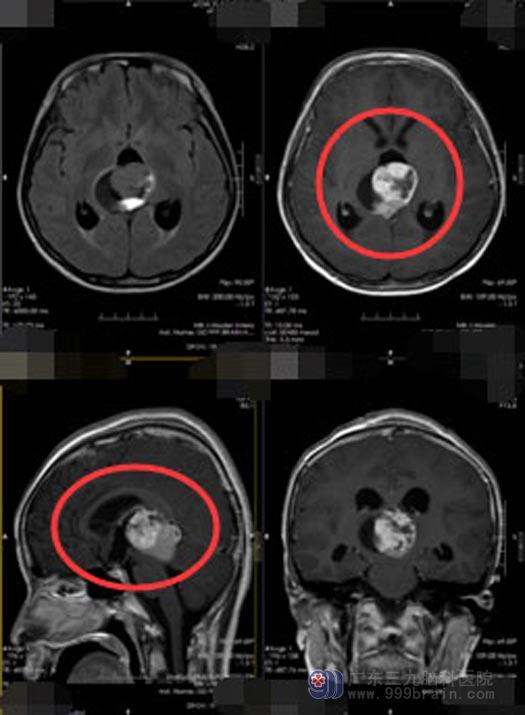

近一个月来,小韩的精神状态越来越差,反应迟钝伴肢体乏力,逐渐发展为不能行走。父母这才开始着急。当地医院头颅MR提示:松果体区占位,伴梗阻性脑积水。医生说:松果体区最常见的肿瘤是生殖细胞瘤,75%的为恶性肿瘤,压迫了脑脊液的循坏通路导致脑积水,就诊时几乎所有患者都会出现典型的脑积水症状和体征:头痛、呕吐、嗜睡、记忆障碍,瘤体较大的患者还可出现耳鸣、听力障碍和步态不稳、共济失调、眼球水平震颤等,如果脱落的肿瘤细胞沿脑脊液播散,还可累及神经根和脊髓;由于松果体区肿瘤位置深在,周围有重要的神经和血管,多年来一直被神经外科医师视为难度大的手术之一。一家人一下子慌了神,他们明白,找对医院、找对专家对于孩子的治疗非常重要。

▲手术前